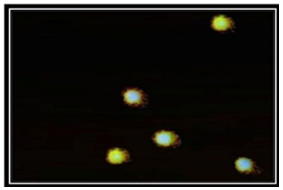

In this study, it was cleared that no significant DNA damage was established in the negative control group. In contrast, patulin induces significant DNA damage in the liver of rats (Positive control). These results show that patulin is genotoxic at the injected dose and liver is its important target organ. Cells in the Negative control animals appeared mostly with no comet. DNA was tightly compressed and maintained the circular disposition of the normal nucleus (Figure2).

The nuclear DNA in the positive control group has different profile. It was altered with the appearance of a fluorescent streak extending from the nucleus and the number of damaged DNA increases in liver cells (Figure3).

By means of the comet assay, the present study has illustrated some of the DNA changes in liver cells of rats subsequent to patulin. In undamaged liver cells, the DNA was tightly compressed and preserved the circular disposition of the normal nucleus. After patulin injection the profile of the nuclear DNA was changed with the presence of a comet that had a bright head and tail, thus allowing the cells' discrimination from those that had normal DNA. Comet assay was used to reveal DNA damage such as strand breaks and DNA-protein cross-links. Cross-links may stabilize chromosomal DNA and inhibit DNA migration (Merk & Speit, 1999; Yousef, Omar, El-Guendi, &Abdelmegid, 2010).